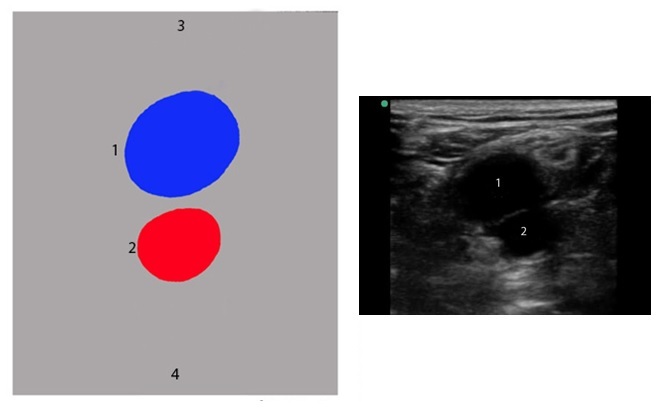

深部静脈血栓症(DVT)と画像膝窩血管の図

膝窩静脈

膝窩動脈

脚の後面

脚の前面